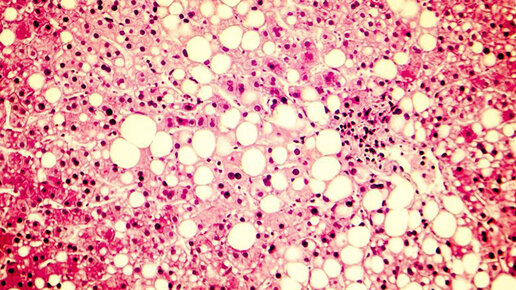

Неалкогольный жировой гепатоз(неалкогольная жировая болезнь печени, НЖБП) имеет несколько стадий - неалкогольный стеатоз, неалкогольный стеатогепатит, цирроз и рак печени. Суть данного патологического состояния заключается в избыточном накоплении жиров (преимущественно триглицеридов) в ткани печени. Успех лечения неалкогольного жирового гепатоза зависит от стадии заболевания, общего состояния организма и наличия сопутствующих заболеваний. Как жир попадает в печень? Причины развития неалкогольного...

Содержание Лишний вес, ожирение и связанные с ними болезни — бич современности. Заболеваемость жировым гепатозом за последние 15 лет выросла в 3 раза. По данным учёных, с «жирной печенью» сейчас живут около 30% людей на земле. А это значит, что их ждёт масса проблем со здоровьем. На начальном этапе всё ограничивается подавленностью, раздражительностью и нарушением сна. Но чем дальше болезнь, тем больше осложнений. Лишний жир в печени мешает работе мозга (по последним данным, на 40% повышает риск...